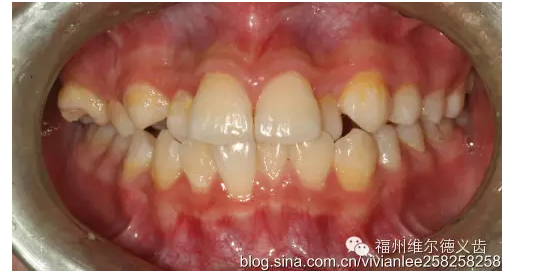

這次機會又沒抓住的話,牙的齲壞開始深了,涉及的牙面多了,這時候單純補牙不行了,需要做嵌體,才能把壞的部分修補好,嵌體要幾百到兩三千不等,有點貴了。

QQ圖片20150725100145.png

QQ圖片20150725100158.png